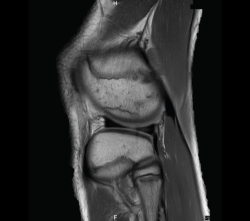

4. Lesiones isquémicas

4.1. Necrosis avascular (NAV)

En la NAV (aséptica, isquémica u osteonecrosis), hay una pérdida del flujo de sangre en el tejido óseo que hace que el hueso muera.

Se produce por un trastorno de la irrigación sanguínea o por lesiones celulares en el hueso y en la médula ósea.

Puede observarse en la RM la disminución de la intensidad de la lesión mucho antes de que se aprecie con otras pruebas diagnósticas (Figura 51).

Figura 51. Corte de secuencia T2 Fat-Sat coronal: lesión osteocondral con necrosis avascular del fragmento óseo.

4.2. Infartos

Los infartos medulares óseos aparecen en el 0,06% de los pacientes a quienes se les ha realizado una RM del aparato locomotor. Se presentan como lesiones segmentarias, puramente medulares, sin afección cortical, normalmente múltiples y que afectan predominantemente a los huesos largos de las extremidades, sobre todo las inferiores. La RM es esencial en el diagnóstico por imagen, apareciendo como lesiones óseas intramedulares de contornos serpiginosos hipo- o isointensos en secuencias T1 e hiperintensos en T2. Por tanto, la RM es el instrumento crucial en las fases iniciales, ya que permite caracterizar las lesiones y proceder a su diagnóstico temprano(19)(Figura 52).

Figura 52. A: corte de secuencia coronal T2 Fat-Sat con infartos óseos en el fémur y la tibia; B: corte de secuencia sagital T1 con infartos óseos en el fémur y la tibia.